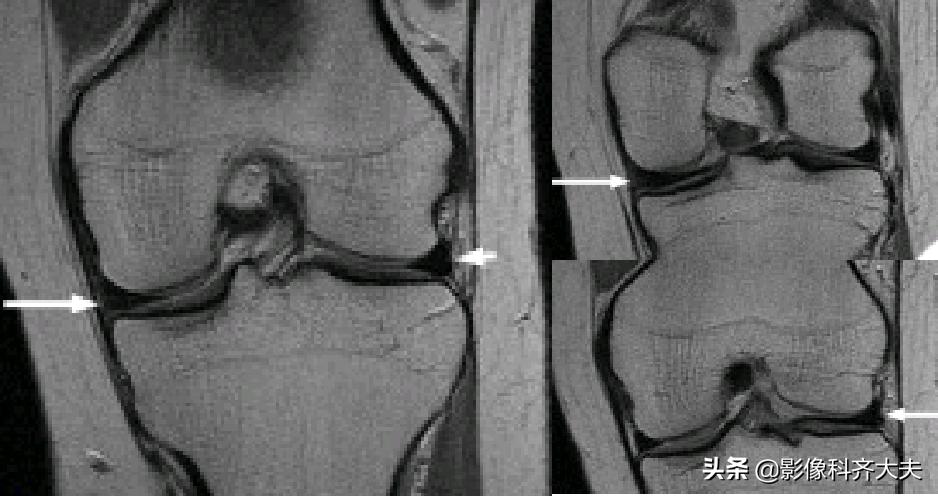

正常半月板MRI冠状位图像